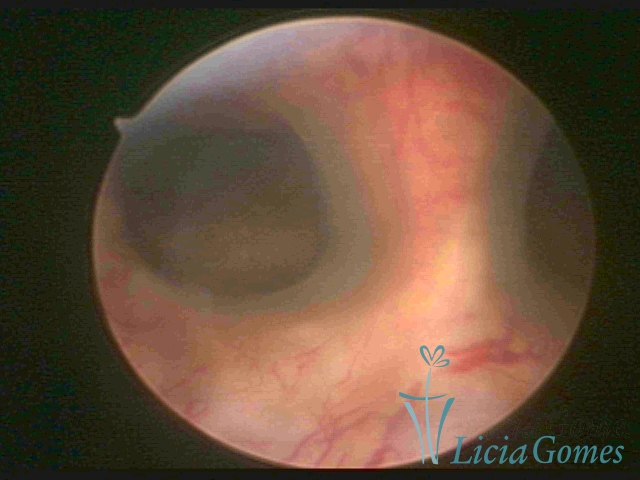

Unicornuate uterus

It presents a tubular cavity with an impaired intracavitary space, resembling the shape of a banana, whose the narrowest edge contains the tubal ostium. The endometrium is compatible with the menstrual cycle and the cervical canal is normal, in structure and trophism.